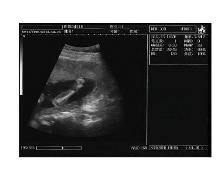

Galería de Imágenes Clínicas

Sonolife 9618